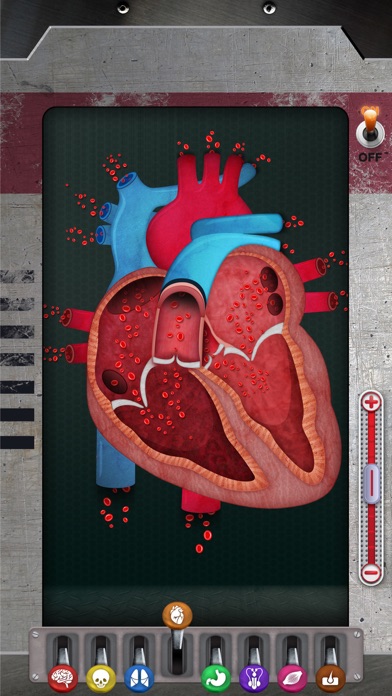

7. Découvrez les globules blancs, les plaquettes et les globules rouges ainsi que les rôles qu'ils jouent pour nous maintenir en bonne santé.